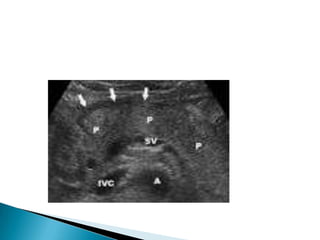

RUQ US

Thicken gallbladder wall

Pericholecystic fluid

Gallstones or sludge

Sonographic murphy sign

HIDA scan-more sensitive & specific than US